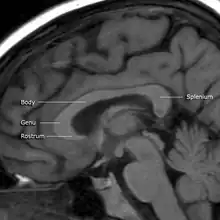

MRI of corpus callosum and its named parts

The corpus callosum has four main parts – individual nerve tracts that connect different parts of the hemispheres. These are the rostrum, the genu, the trunk or body, and the splenium.[4] Fibres from the trunk and the splenium, known together as the tapetum ("carpet"), form the roof of each lateral ventricle.[6]

The front part of the corpus callosum, towards the frontal lobes, is called the genu ("knee"). The genu curves downward and backward in front of the septum pellucidum, diminishing greatly in thickness. The lower, much thinner part is the rostrum and is connected below with the lamina terminalis, which stretches from the interventricular foramina to the recess at the base of the optic stalk. The rostrum is named for its resemblance to a bird's beak.

The end part of the corpus callosum, towards the cerebellum, is called the splenium. This is the thickest part, and overlaps the tela choroidea of the third ventricle and the midbrain, and ends in a thick, convex, free border. Splenium translates as "bandage" in Greek.

The trunk of the corpus callosum lies between the splenium and the genu.